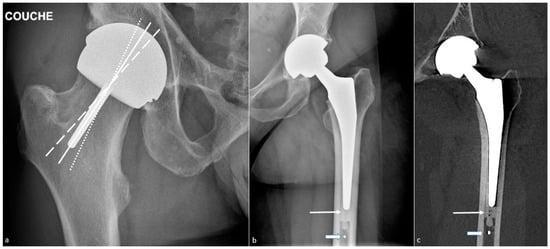

4.2.2. Imaging

4.3. Osteolysis and Loosening

4.3.3. Radiographs, Tomosynthesis, and CT